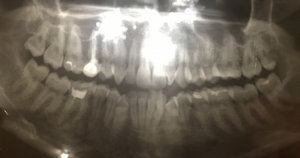

Очень сложно определить, но все Ваши симптомы говорят и свищевом выходе. То есть, на верхушках зуба имеется воспалительный процесс.

Необходимо обратиться к врачу, сделать рентген-снимки и выявить точную причину.